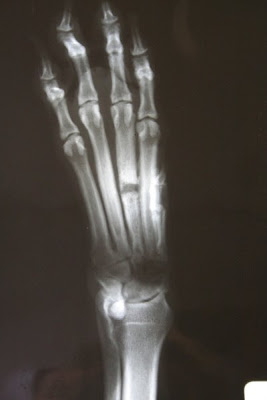

Quark fik taget kontrolrøgten af sit ben. Jeg var meget MEGET nysgerrig efter at vide, hvordan det så ud. Her er resultatet: Som det tydeligt ses, er det groet perfekt LIGE sammen, men det er stadig meget “blødt” og derfor skal han stadig holdes i forholdsvis i ro (ingen agility og ingen hurtig susen afsted). Dyrlægen anbefalede 8 uger endnu inden jeg gav ham lov til at træne maximalt igen. Men jeg er rigtig RIGTIG glad for den nyhed. Bulen ovenpå hans ben, bliver mindre med tiden, men skyldes IKKE betændelse, men at bløddelene bliver lidt irriteret af den nye knogledannelse og så er der også noget ar-væv i forbindelse med at det er lige der, hjørnetanden er gået igennem.